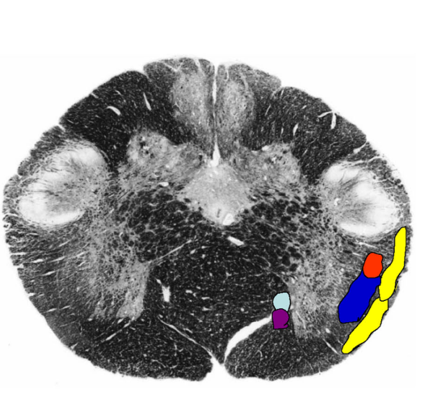

Describe what happens to these structures @ midolivary Levels:

Restiform body

Arcuate nuclei

Nucleus gracilis/ cuneatus

Lateral cuneate nucleus

Rubrospinal, reticulospinal and vestibulospinal tracts

anterior spinocerebellar tract

Ventral Trigeminothalamic tract

Similar Position:

Spinal nucleus and tract

Pyramidal tract,

Medial Lemniscus ,

tectospinal tract

medial Ionitudinal fasciculus

anteroateral system are in similar positions.

Midolivary Levels:

Restiform body enlarges

found in the ventral aspect of the pyramid.

nuclei = continuous w/ pontine nuclei → cerebellum

as ventral external arcuate fibers and the striae medullares.

no longer present;

vestibular nuclei adopt their position

may still be present

in lateral position.

present.

lateral to medial lemniscus still.